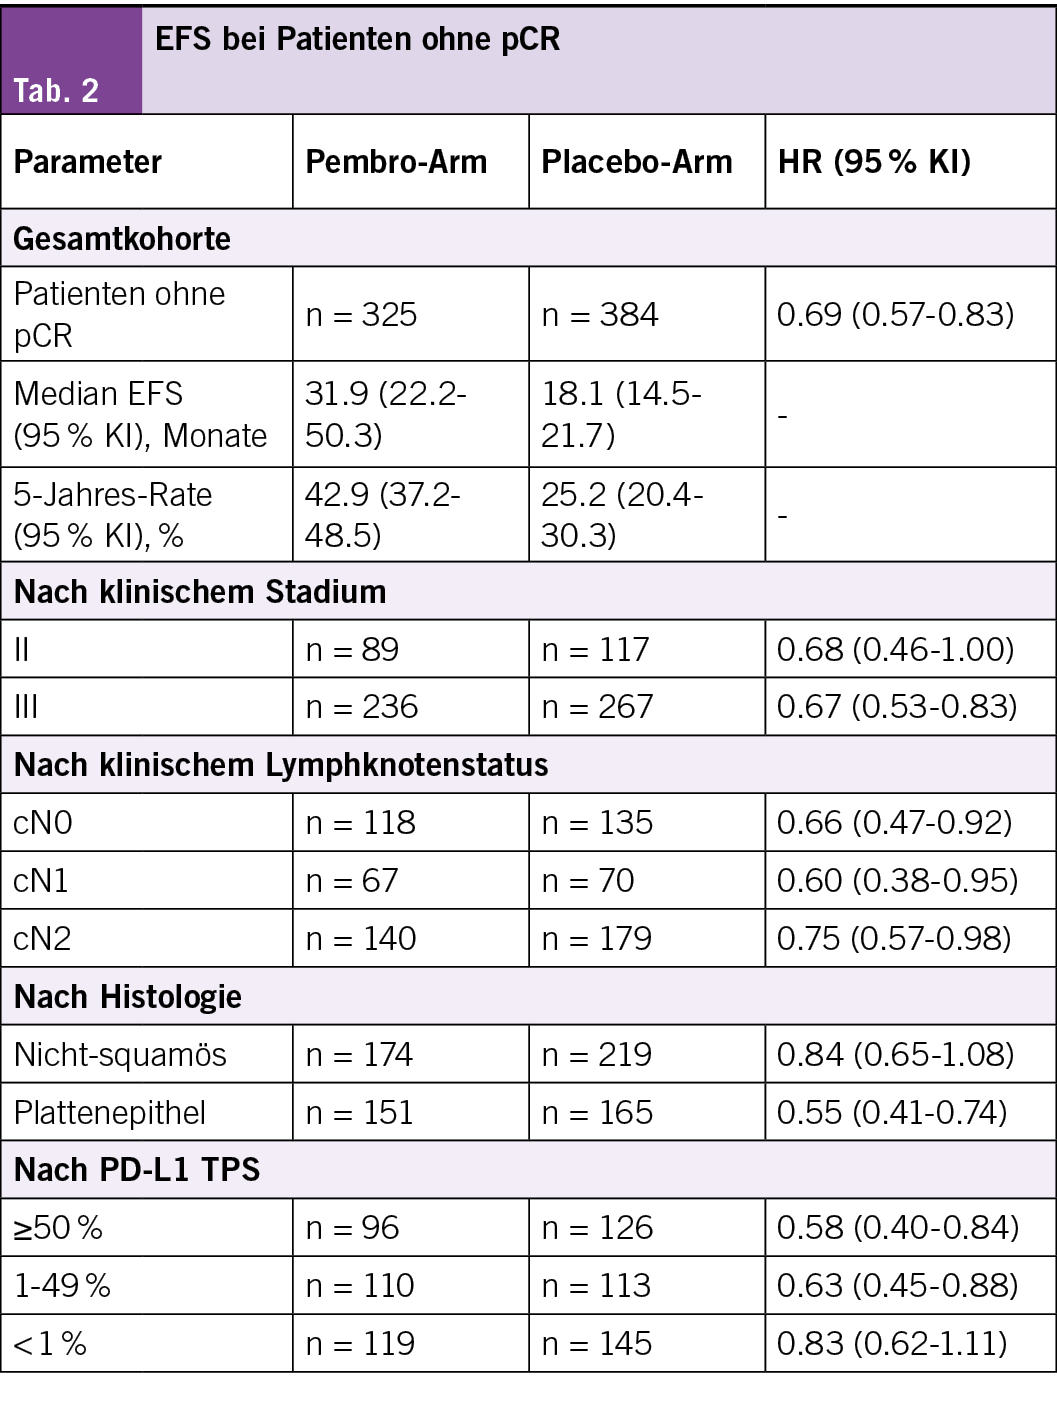

Daten sprechen für den Einsatz der perioperativen Pembro-Therapie plus neoadjuvanter Chemotherapie bei resektablem NSCLC im Frühstadium

Martin Reck, et a. 222MO Exploratory analysis of participants without pathological complete response (pCR) in the KEYNOTE-671 study of perioperative pembrolizumab (pembro) in early-stage NSCLC after 5 years of follow-up

Vorbemerkungen

In der Phase-3-Studie KEYNOTE-671 bei nicht-kleinzelligem Lungenkrebs (NSCLC) im Frühstadium verbesserte laut den Studienautoren die perioperative Gabe von Pembrolizumab in Kombination mit einer neoadjuvanten Chemotherapie (Chemo) das ereignisfreie Überleben (EFS), das Gesamtüberleben (OS), das signifikante pathologische Ansprechen und die pCR im Vergleich zur neoadjuvanten Chemotherapie signifikant. Das EFS war in explorativen Analysen bei Teilnehmern, die keine pCR erreichten, verlängert (HR, 0,69; 95 % KI, 0,55–0,85).

Die Autoren berichten über die Ergebnisse bei Pt. ohne pCR aus der KEYNOTE-671-Studie nach 5 Jahren Nachbeobachtung.

Studiendesign

• Teilnahmeberechtigte Patienten im Alter von ≥ 18 Jahren mit zuvor unbehandeltem, resezierbarem NSCLC im Stadium II–IIIB (N2) gemäss AJCC v8 wurden im Verhältnis 1:1 randomisiert und erhielten

• entweder 200 mg Pembrolizumab oder Placebo alle 3 Wochen plus Chemotherapie über 4 Zyklen, gefolgt von einer Operation und adjuvanter Behandlung mit Pembrolizumab oder Placebo alle 3 Wochen über bis zu 13 Zyklen (≥ 9 Monate).

• Zu den primären Endpunkten gehörten die EFS gemäss RECIST v1.1 durch den Prüfer und das OS; zu den sekundären Endpunkten gehörte die pCR durch einen verblindeten Pathologen eines zentralen Labors.

Behandlungsergebnisse

• Von den 397 Patienten, die der Pembro-Gruppe zugewiesen wurden, und den 400 Patienten in der Placebo-Gruppe erreichten 72 (18,1 %) bzw. 16 (4,0 %) eine pCR; davon erhielten 67 Patienten (93,1 %) in der Pembrolizumab-Gruppe und 15 Patienten (93,8 %) in der Placebo-Gruppe mindestens eine adjuvante Dosis und 47 (65,3 %) bzw. 12 (75,0 %) schlossen die adjuvante Therapie ab.

• Die mediane Zeit von der Randomisierung bis zum Datencutoff (3. Juli 2025) betrug bei Patienten ohne pCR 60,2 (Bereich: 42,6–85,8) Monate.

• Die HR für das EFS betrug 0,69 (95 % KI: 0,57–0,83) zugunsten der Pembro- gegenüber der Placebo-Gruppe (Tabelle).

• Die OS-Daten für diese Untergruppe sind noch nicht ausgereift.

Verträglichkeit

• Behandlungsbedingte unerwünschte Ereignisse (UE) des Grades 3 traten bei 143 von 324 (44,1 %) mit Pembro behandelten Patienten und bei 146 von 383 (38,1 %) mit Placebo behandelten Patienten auf.

• Immunvermittelte unerwünschte Ereignisse (UE) des Grades 3 und Infusionsreaktionen traten bei 21 (6,5 %) bzw. 7 Patienten (1,8 %) auf. (Tab. 2)

Fazit

Bei Patienten ohne pCR in der KEYNOTE-671 verlängerte laut den Studienautoren die perioperative Pembro-Therapie plus neoadjuvante Chemotherapie auch nach 5 Jahren Nachbeobachtungszeit weiterhin das EFS, unabhängig von den klinischen Ausgangsmerkmalen. Diese Daten sprechen für den Einsatz der perioperativen Pembro-Therapie plus neoadjuvanter Chemotherapie bei resektablem NSCLC im Frühstadium.